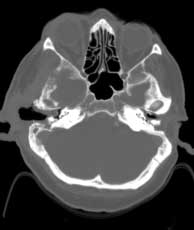

Axial CT bone windows

Extensive, permeative destruction involving the squamous portion of the right temporal bone (a). Post-op bilateral mastoidectomies (b).